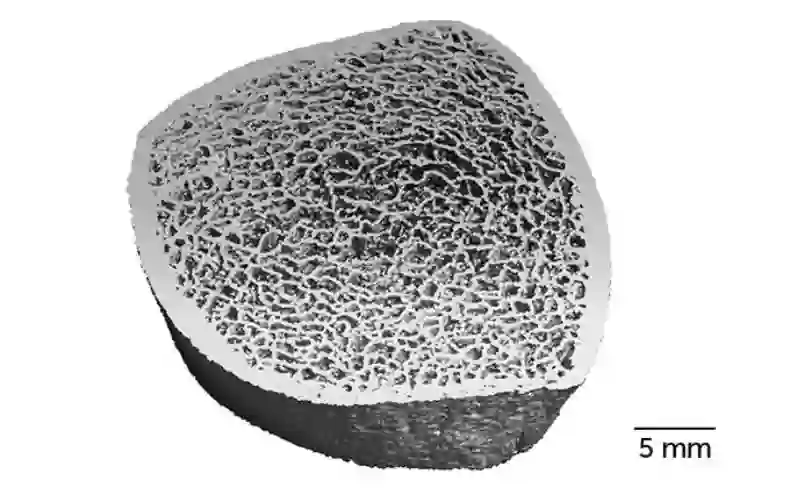

在这项工作中,研究团队通过使用高分辨率外围定量计算机断层扫描(HR-pQCT),在 61 微米尺度上(比人类头发还要细)测量了宇航员的 3D 骨骼微结构,对小腿胫骨的骨骼结构和小臂的半径进行成像。

图|使用高分辨率计算机断层扫描成像使研究人员能够研究宇航员骨骼中的 3D 骨骼微结构(此处显示的胫骨示例)。细微的细节可以揭示骨密度和强度的变化。